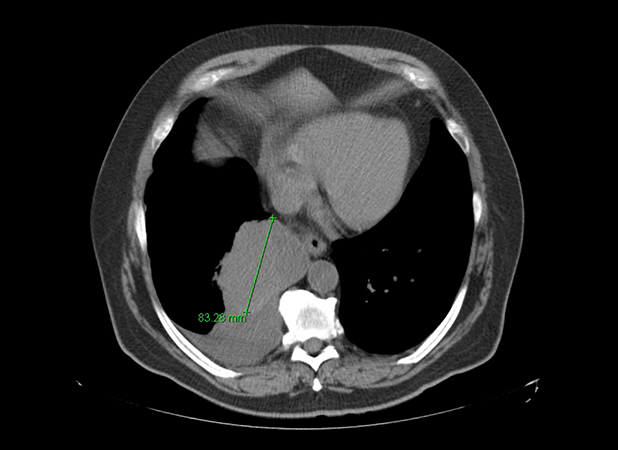

Clinical History: A 68-year-old-man never-smoker presented with a fever, cough, and rhinorrhea. The patient was treated for a presumed pneumonia; however, his symptoms persisted despite multiple courses of antibiotics. He subsequently underwent a chest CT scan, which revealed a solitary medial right lower lobe mass measuring 10.9 x 8.3 cm, concerning for a primary lung malignancy (Figures 1 and 2). No other abnormalities were seen. Biopsy was attempted, but the specimen only showed a minute focus of epithelioid malignant cells that was insufficient for further workup. The patient underwent right lower lobe lobectomy for diagnosis and curative-intent therapy. The patient has no history of prior malignancy.